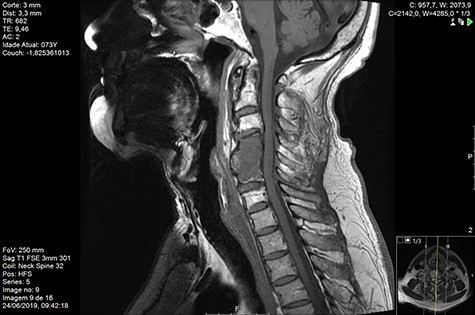

Computed tomography (CT) (Figs 1–3) and magnetic resonance imaging (MRI) (Figs 4–6) of the cervical spine were performed and revealed a lytic lesion involving most of C4, C5 and C6 vertebral bodies with bilateral extension to the posterior spinal elements of C4 and C5 and complete disruption of C4-C5 and C5-C6 intervertebral discs.

The Spinal Instability Neoplastic Score (SINS) [4, 6, 7] for assessing spinal instability from metastatic disease was used and the lesion was deemed unstable (SINS 13), with impending risk of increased neurological damage.

MRI and CT scans performed at 90 days post-radiation therapy showed an arrest of further progression of instability and resolution of the lytic lesion (Figs 7–13).